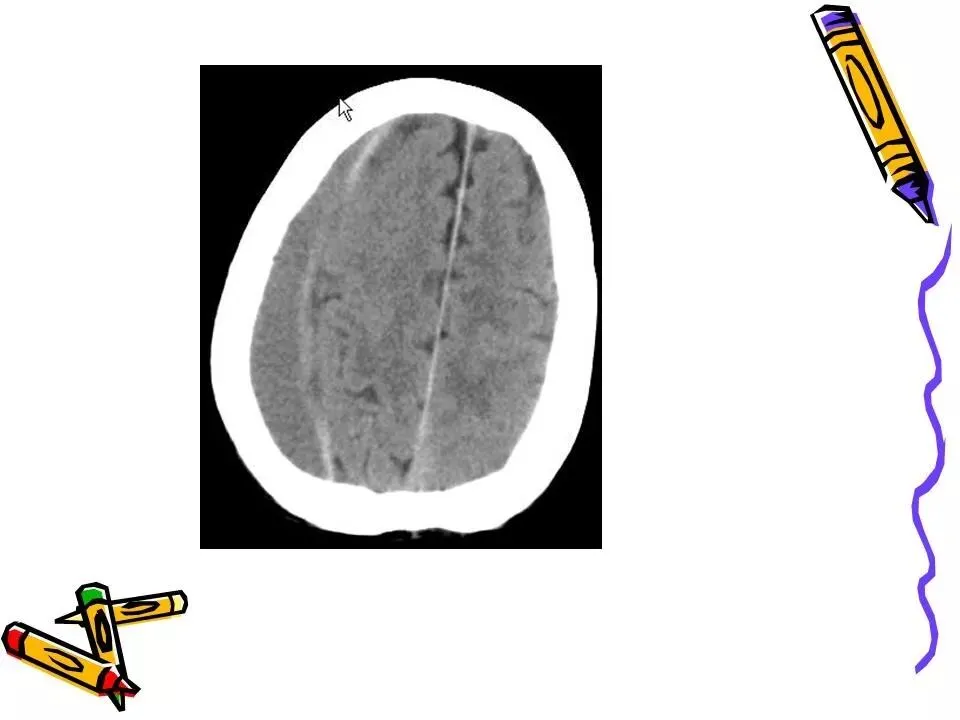

>常见颅脑外伤CT诊断(PPT)

常见颅脑外伤CT诊断(PPT)